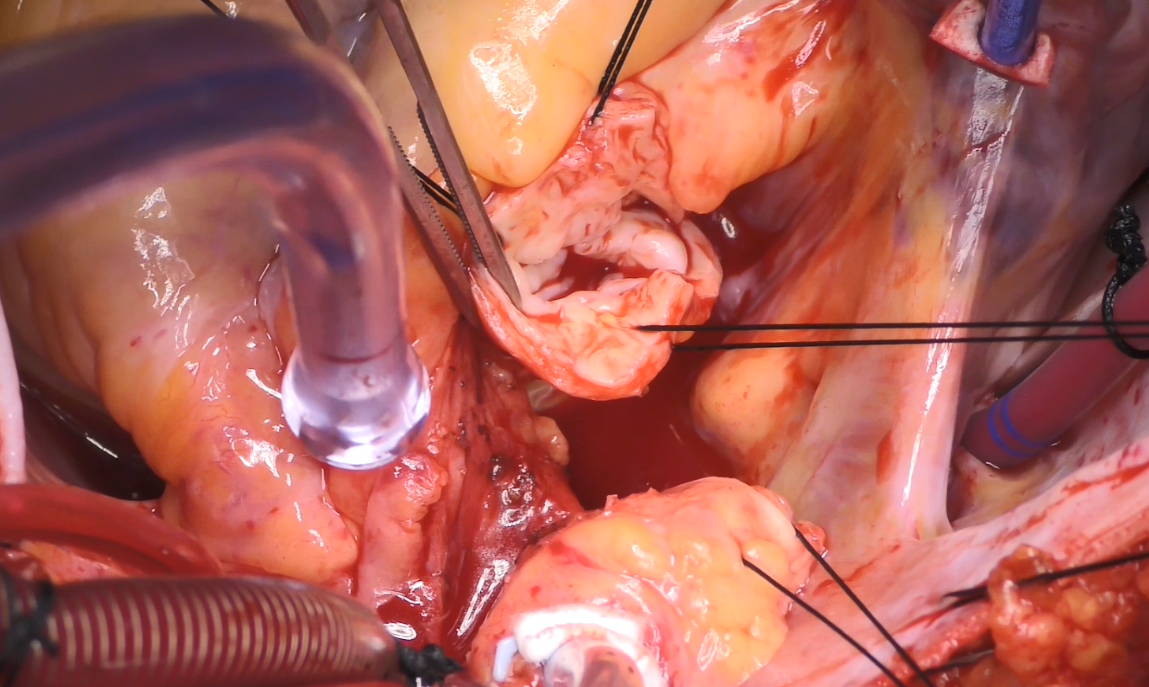

Pictured: "Adult Supravalvular Aortic Stenosis: Modified Three-Patch Aortic Root Reconstruction"

- Adult Supravalvular Aortic Stenosis: Modified Three-Patch Aortic Root Reconstruction